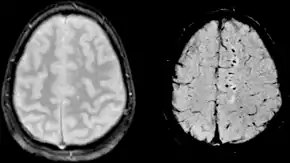

Images of CAA collected at 1.5 T. Left, conventional T2* (TE=20 ms), center, SWI processed magnitude image (TE=40 ms) and right, SWI phase image (TE=40 ms)

Gradient recalled echo (GRE) imaging is the conventional way to detect hemorrhage in CAA, however SWI is a much more sensitive technique that can reveal many micro-hemorrhages that are missed on GRE images.[7] A conventional gradient echo T2*-weighted image (left, TE=20 ms) shows some low-signal foci associated with CAA. On the other hand, an SWI image (center, with a resolution of 0.5 mm x 0.5 mm x 2.0 mm, projected over 8mm) shows many more associated low-signal foci. Phase images were used to enhance the effect of the local hemosiderin build-up. An example phase image (right) with yet higher resolution of 0.25 mm x 0.25 mm x 2.0 mm shows a clear ability to localize multiple CAA-associated foci.